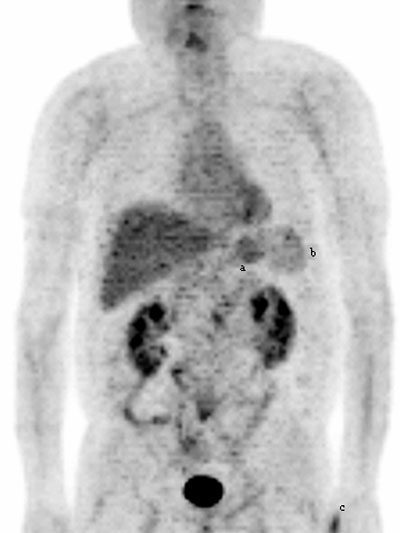

Fig. 11. - Imágenes coronal y lateral de tomografía por emisión de positrones de cuerpo completo. Varón de 60 años con antecedentes familiares de diversas tumoraciones. Se observa hipermetabolismo fisiológico de la [18]FDG en estómago (a), hígado y bazo (b). Asimismo se aprecia aumento de la actividad de la [18]FDG en n pulgar de mano izquierda (c), que se correspondía con importante tendinitis en dicha localización. volver